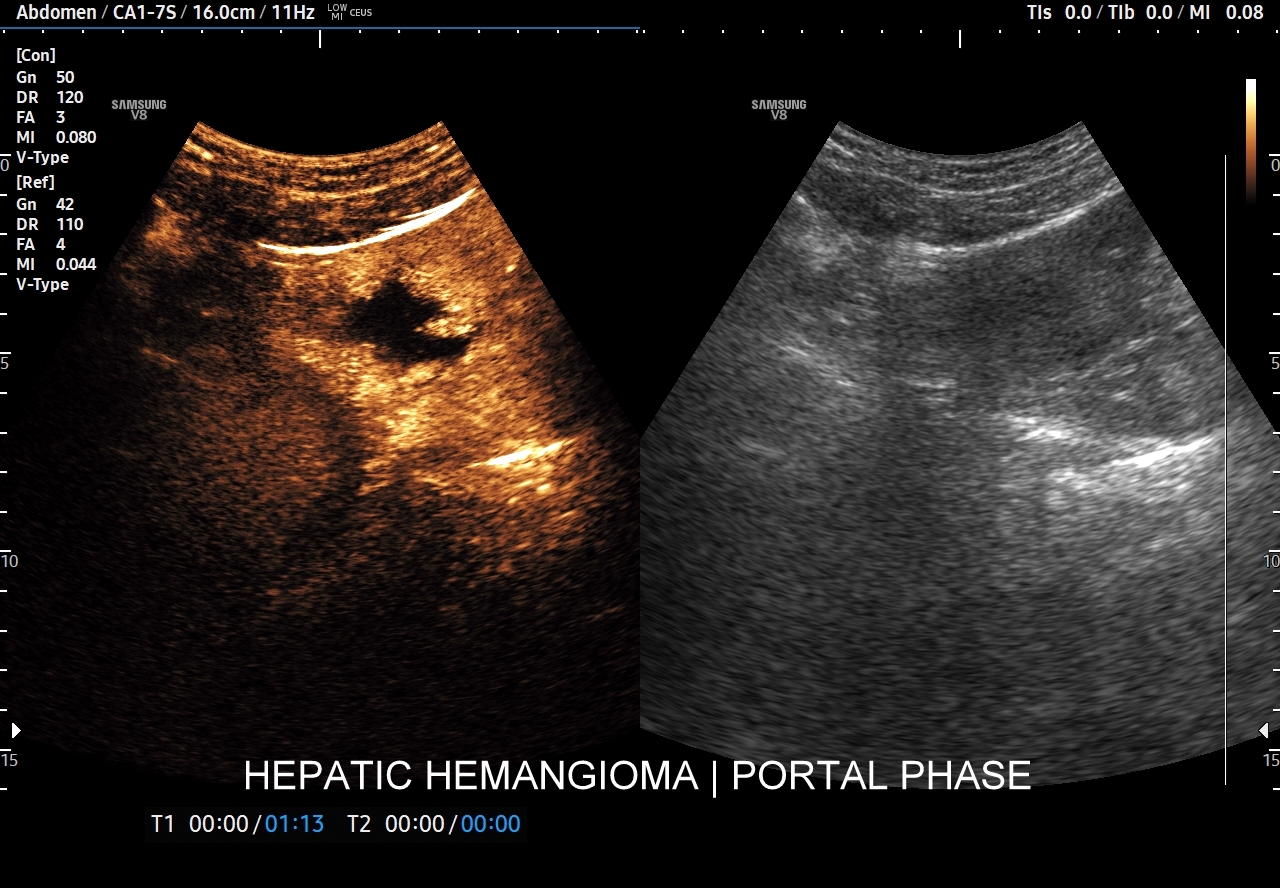

Najbardziej charakterystyczną cechą naczyniaka wątroby w badaniu CEUS jest jego wypełnianie w postaci guzkowej (ang. peripheral nodular enhancement) od obwodu ku centrum zmiany (ang. centripetal). Szybkość wypełniania bywa różnorodna, może być powolna lub szybka. W przypadku szybkiego wypełniania (tzw. flash-filling), w celu wykazania charakterystycznego centrypetalnego wypełniania niezbędna może być postprocessing’owa analiza poklatkowa zapisanego nagrania badania. W fazie późnej naczyniak wątroby pozostaje izowzmocniony lub hyperwzmocniony w stosunku do natywnego miąższu wątroby.

W przypadku dużych naczyniaków obszary, które uległy wykrzepianiu pozostają awaskularne przez wszystkie fazy badania CEUS, tj. nie wypełniają się kontrastem (nonenhancing). W przeciwieństwie do powyższego konstelacja, w której to w fazie wczesnej pojawia się wzmocnienie, a następnie w fazie wrotnej lub późnej ulega wypłukaniu (hypoenhancement) świadczy o cechach złośliwych diagnozowanej zmiany ogniskowej w wątrobie i wyklucza rozpoznanie naczyniaka.